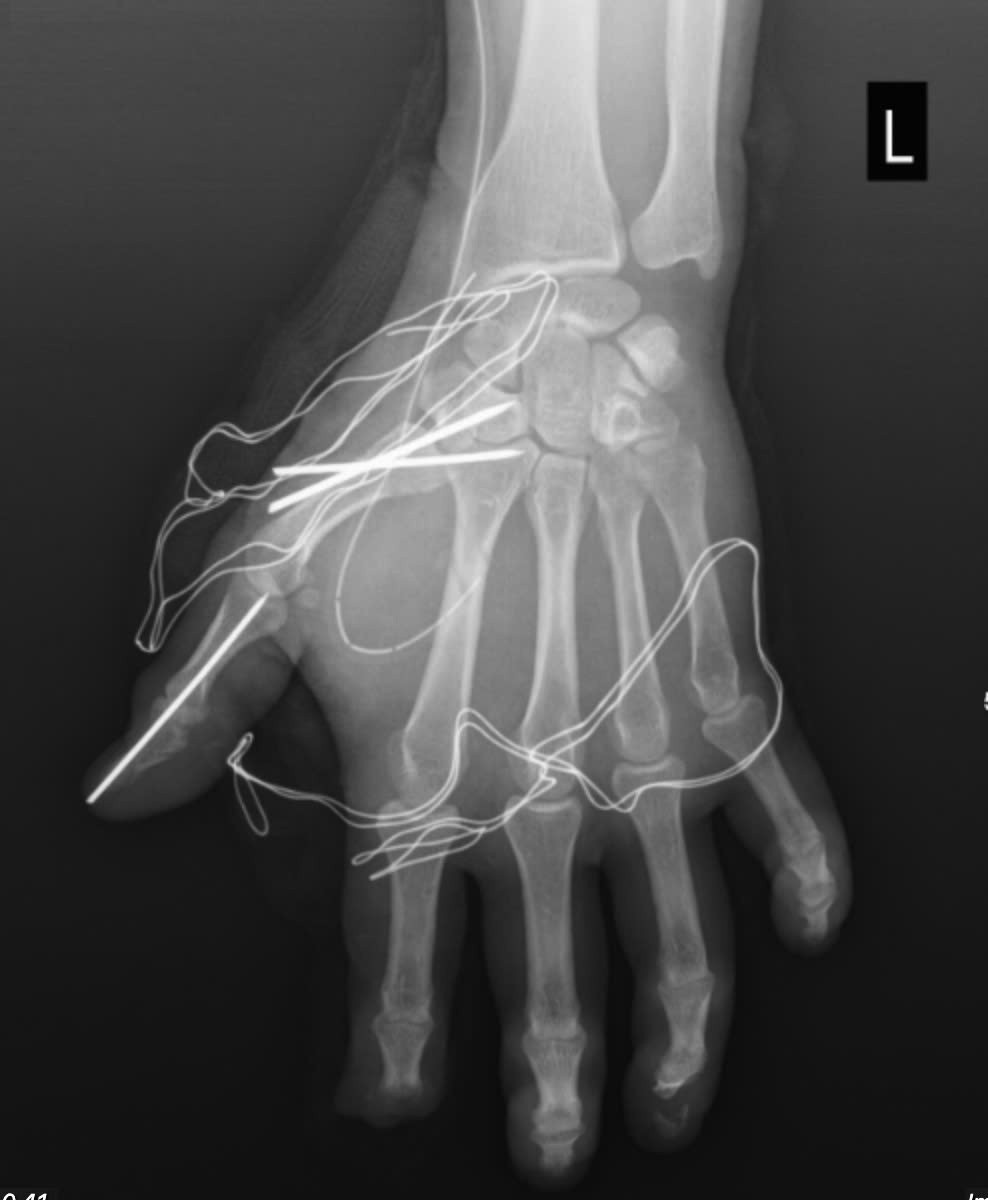

Trong quá trình phẫu thuật, các bác sĩ Khoa Phẫu thuật chấn thương chỉnh hình và y học thể thao đã tiến hành cắt lọc tổ chức dập nát, lấy bỏ dị vật trên bàn tay của người bệnh. Đồng thời, các bác sĩ làm sạch vết thương, bảo tồn tối đa cấu trúc gân, thần kinh và mạch máu còn lại cho người bệnh. Cuối cùng, các bác sĩ đã cố định xương gãy và khớp bị trật cho người bệnh.

Sau phẫu thuật, người bệnh tiếp tục được điều trị tại khoa Phẫu thuật chấn thương chỉnh hình và Y học thể thao – Bệnh viện E và theo dõi sát nguy cơ nhiễm trùng và hoại tử thứ phát, đồng thời lên kế hoạch phục hồi chức năng nhằm giúp người bệnh sớm trở lại sinh hoạt bình thường.

Tổn thương sau phẫu thuật - Ảnh BVCC